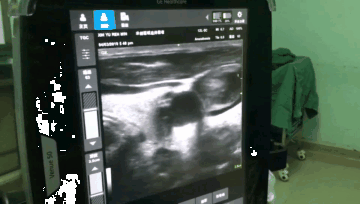

该患者颈内静脉有血栓

特别是现在很多肿瘤患者需要使用深静脉进行化疗治疗,我们就更需要使用超声来探查静脉。我们科最近几年碰到过好几例患者颈内静脉内全是癌栓和血栓的情况,如果贸然进行静脉穿刺可能会导致栓子脱落导致急性肺栓塞,癌栓播散甚至患者死亡。